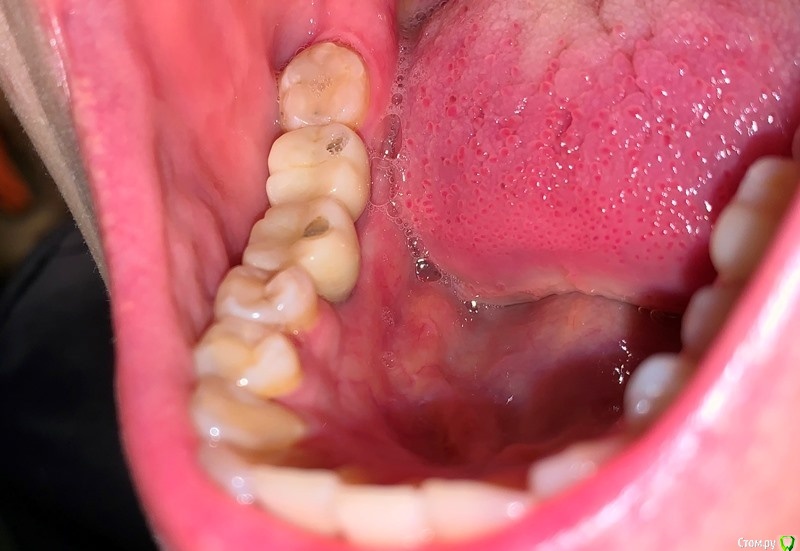

Diana1974 Опубликовано 8 января, 2021 Поделиться Опубликовано 8 января, 2021 Добрый день! Подскажите, нормально ли это и нужно ли просить что-то переделывать? 2 недели назад поставили коронки на импланты, до первого приема пищи всё было хорошо, десна выглядит нормальной, но места установки постоянно ноют, еда очень сильно набивается и также вызывает сильное давление и боль, жесткая еда и холод вызывают пульсацию. Врач сказал, всё хорошо и будет еще затягивать их. Ноющая боль появлялась еще с момента установки формирователей (в июле), но врач также говорил, что всё хорошо прижилось и идет по плану. На втором снимке стрелочкой указала сопутствующую проблему: беспричинная сильная боль и пульсация четко в десне между передними зубами, которая то утихает, то появляется вновь (стоматолог и парадонтолог осматривали, по их части проблем нет, зубы, между которыми боль ни разу не лечились и на данный момент здоровы), проблеме 3 месяца, предпринимала много чего, в итоге меня отправляют к стоматоневрологу. Всё это может быть связано с имплантами или наоборот все эти проблемы не относятся к стоматологии и нужно искать причину у невролога? Ссылка на комментарий

dentikl Опубликовано 8 января, 2021 Поделиться Опубликовано 8 января, 2021 Добрый день! Всё это может быть связано с имплантами или наоборот все эти проблемы не относятся к стоматологии и нужно искать причину у невролога?семечки любите? Ссылка на комментарий

Diana1974 Опубликовано 8 января, 2021 Автор Поделиться Опубликовано 8 января, 2021 семечки любите?нет, и не ела уже давно Ссылка на комментарий

dentikl Опубликовано 9 января, 2021 Поделиться Опубликовано 9 января, 2021 нет, и не ела уже давнопокажите фото передних зубов Ссылка на комментарий

Diana1974 Опубликовано 9 января, 2021 Автор Поделиться Опубликовано 9 января, 2021 Где именно, уточните Больше возле дальнего имплантата или ближнего? Больше всего застревает со стороны языка в промежутке между коронками, туда еда попадает так, что очень сложно достать без промывки ирригатором и нити, и соответственно находясь вне дома еда очень здорово раздражает десну (может это нормально, но я думала, что можно будет полноценно всё есть не зная боли).По поводу боли не могу определенно сказать, что она исходит от конкретной коронки, но она совершенно четко присутствует вне приемов пищи. Ссылка на комментарий